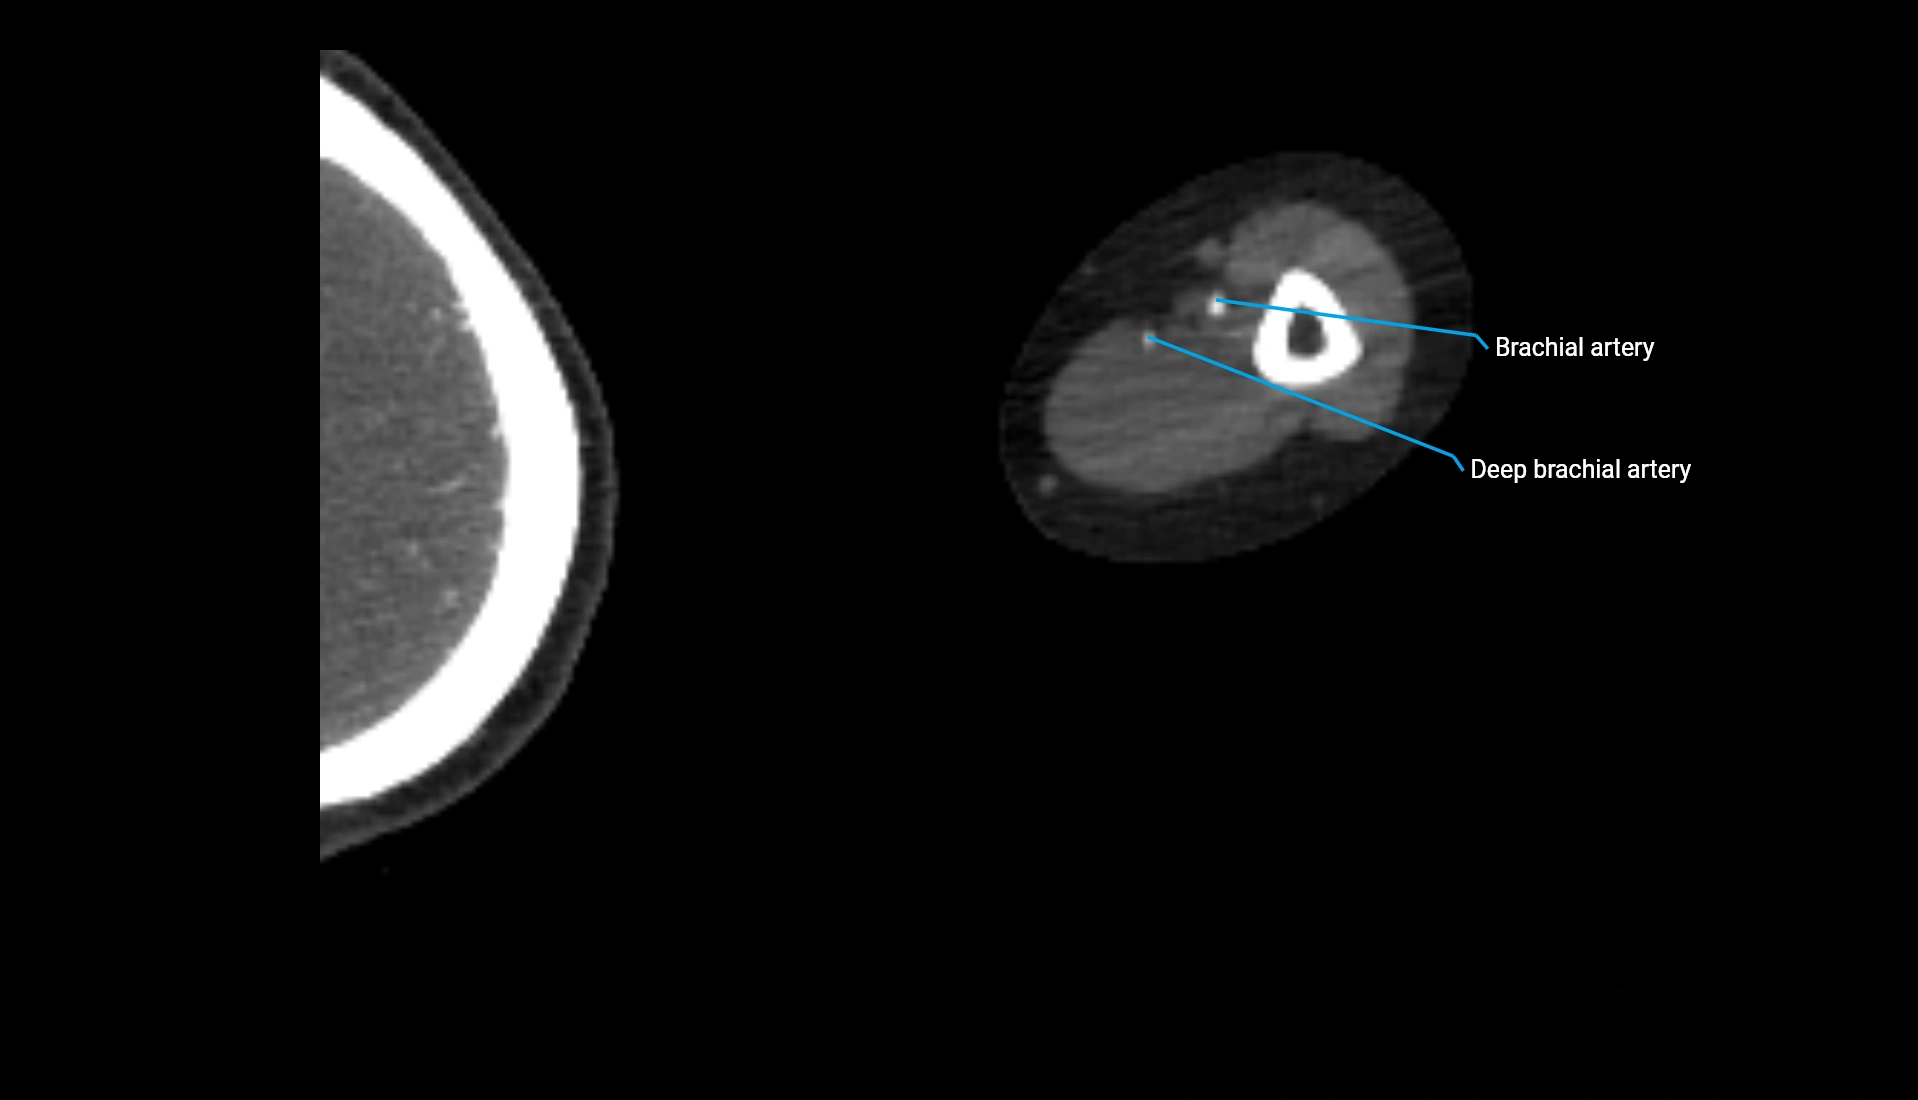

CT Appearance

Non-Contrast CT:

• Cortex: High-density, sharply defined

• Subchondral bone: Dense cancellous matrix

• Articular surface: Smooth concave contour articulating with the capitellum

• Excellent for evaluating bone integrity, alignment, and subtle fractures